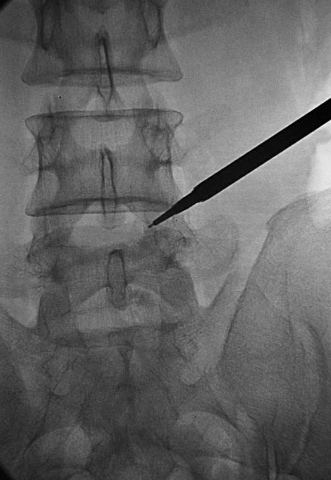

置入1级导杆:使头端到达第一靶点(图15)。

图15 置入1级导杆A.前后位透视头端到达第一靶点;B.侧位透视头端抵达L5椎体后上缘。

依次置入1~3级扩张管扩张软组织通道,3级扩张管在椎间孔外受阻(图16)。

图16 依次置入1级~3级扩张管,扩张软组织通道,3级扩张管在椎间孔外受阻。